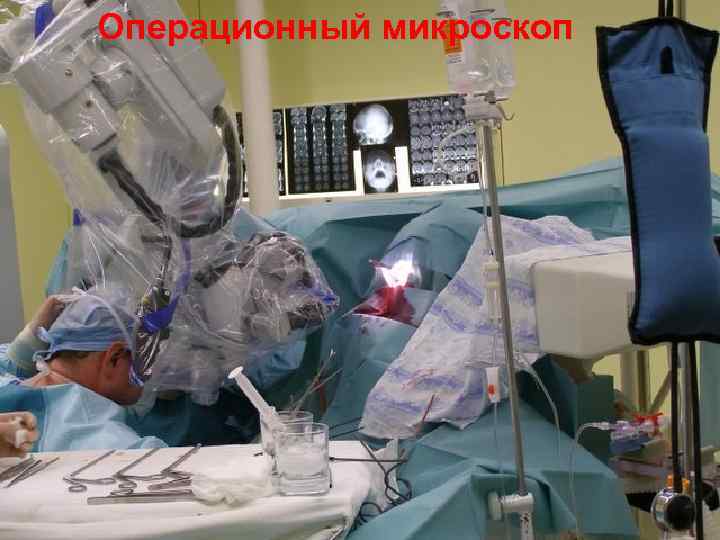

Операционный микроскоп 43

Операционный микроскоп 44